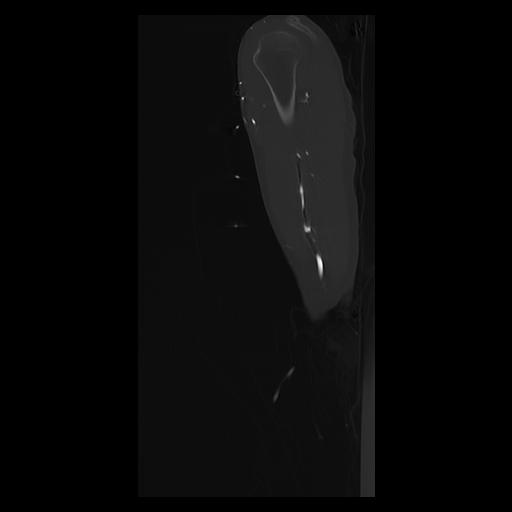

33 PULMON,CE,Sagittal,3.000,PULMON,Sagittal,